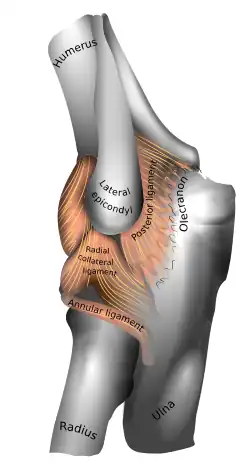

Left: anterior and ulnar collateral ligaments

Right: posterior and radial collateral ligaments

The elbow, like other joints, has ligaments on either side. These are triangular bands which blend with the joint capsule. They are positioned so that they always lie across the transverse joint axis and are, therefore, always relatively tense and impose strict limitations on abduction, adduction, and axial rotation at the elbow.[8]

The ulnar collateral ligament has its apex on the medial epicondyle. Its anterior band stretches from the anterior side of the medial epicondyle to the medial edge of the coronoid process, while the posterior band stretches from posterior side of the medial epicondyle to the medial side of the olecranon. These two bands are separated by a thinner intermediate part and their distal attachments are united by a transverse band below which the synovial membrane protrudes during joint movements. The anterior band is closely associated with the tendon of the superficial flexor muscles of the forearm, even being the origin of flexor digitorum superficialis. The ulnar nerve crosses the intermediate part as it enters the forearm.[8]

The radial collateral ligament is attached to the lateral epicondyle below the common extensor tendon. Less distinct than the ulnar collateral ligament, this ligament blends with the annular ligament of the radius and its margins are attached near the radial notch of the ulna.[8]